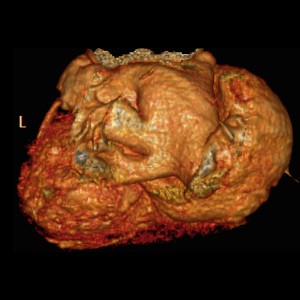

Cor triatriatum sinister - A rare cause of left heart obstruction on MDCT

Cor triatriatum sinister - A rare cause of left heart obstruction on MDCT

Cor triatriatum sinister - A rare cause of left heart obstruction on MDCT

Cor triatriatum sinister - A rare cause of left heart obstruction on MDCT